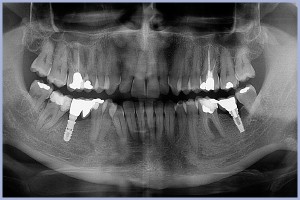

La situazione degli impianti era quella testimoniata dalla ortopantomografia (Fig. 1):

- Fig. 1 – Ortopantomografia a distanza rispettivamente di 6 anni e mezzo e 5 anni e mezzo dall’inserimento degli impianti

Si nota come non vi sia cono di riassorbimento a livello dell’impianto Leone, evento che purtroppo si presenta nel caso dell’impianto con connessione ad esagono esterno. Si aggiunga il fatto che la vite di connessione di quest’ultimo si è allentata, provocando la mobilità della corona. Ho dovuto intervenire forando la capsula occlusalmente, per poi “tirare” la vite stessa con il cacciavite da 1,2 mm; questa è sempre un’operazione che induce un po’ di ansia, per il rischio di rovinare l’esagono della vitolina. Lo svitamento della vite di connessione è il motivo per cui, sei anni fa, passai alla metodica Leone.